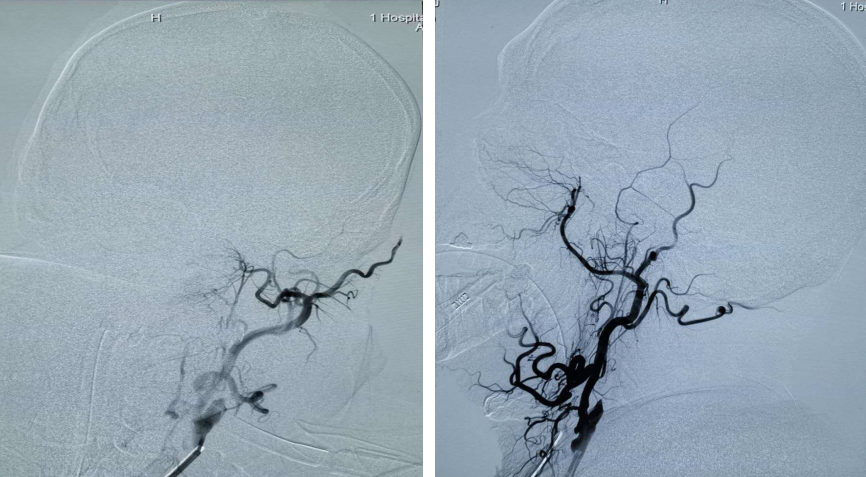

全脑血管造影术提示:左侧颈内动脉起始部闭塞,左侧颈内颅内段未见显影;在颈内动脉起始部采用Rebar-18微导管采用SWIM(支架取栓+抽吸)技术。

支架于血栓充分贴合后取栓系统回收,复查造影示:左侧大脑中动脉远端未见显影;Silverspeed14微导丝携带Rebar-18微导管到达左侧颈内动脉M2段,采用SWIM技术后复查造影血流通畅。

PT导丝携带颈动脉支架通过左侧颈内动脉狭窄处,释放支架后复查造影支架贴壁良好狭窄率不足10%。